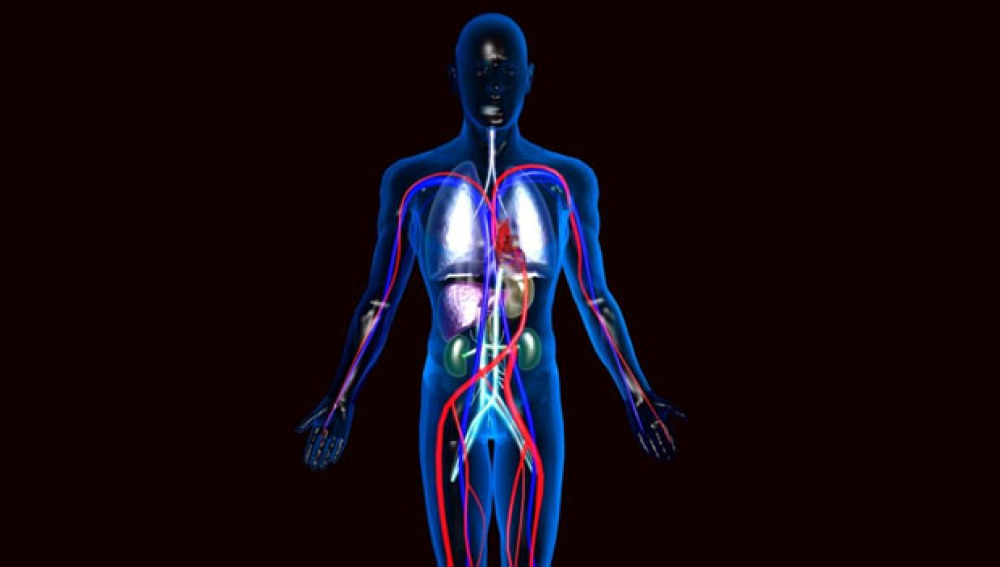

Se trataría de un "órgano" situado por debajo de la capa superficial de la piel, así como en tejidos del intestino, pulmones, músculos, venas y arterias. Hasta ahora, se creía que estas capas del cuerpo eran densos tejidos conjuntivos. Sin embargo, los autores del descubrimiento han identificado una red de compartimentos rellenos de líquido linfático.

Desde hace tiempo se conoce que poco menos de la mitad del líquido del cuerpo humano es intersticial o, dicho de otro modo, son fluidos que se encuentran en el espacio entre las células.

El nuevo estudio propone considerar esta red como un órgano de pleno derecho al igual que, por ejemplo, la piel.

El reconocimiento del intersticio como órgano afectaría directamente al estudio de todos los aparatos del cuerpo, así como a la investigación de los mecanismos de la mayoría de enfermedades.

Los investigadores consideran, por ejemplo, que esta capa de líquido en movimiento explicaría por qué el cáncer se extiende con tanta rapidez.

Según los investigadores, la observación del líquido intersticial "podría convertirse en una poderosa herramienta para elaborar diagnósticos".

Las primeras teorías apuntan a que la función principal del intersticio sería absorber el impacto del movimiento cotidiano de órganos, músculos, venas y arterias. De esta forma, se evitaría la rotura de tejidos por contracciones y fricciones.